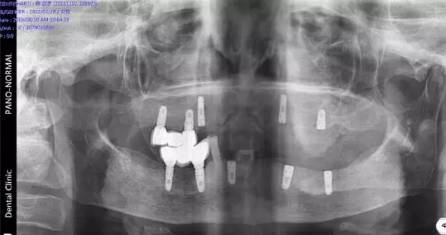

現(xiàn)場北京口腔醫(yī)學會專家、德國專家親自接診,經(jīng)過口腔CT確診,老人全口牙缺失,為其制定CHEESE德國激光種植技術(shù),8根牙根種出滿口好牙,不僅當天種好,還省了錢。

(現(xiàn)場口腔CT拍片)